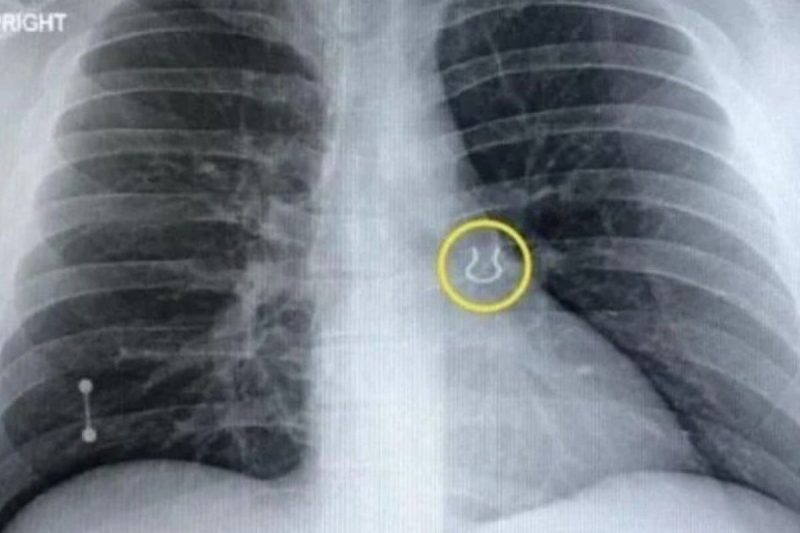

Durante este mês de setembro, o americano Joey Lykins encontrou seu piercing do nariz sumido há cinco anos em outra parte do corpo. Ele foi ao hospital após acordar com tosse e com dificuldade para respirar.

Piercing do nariz perdido foi parar no pulmão do americano – Foto: REPRODUÇÃO/JOEY LYKINS/NY POSTPiercing do nariz perdido foi parar no pulmão do americano – Foto: REPRODUÇÃO/JOEY LYKINS/NY POST

O homem achou que estivesse com pneumonia ou outra doença grave, mas, depois de realizar um raio-x, descobriu que o problema era seu piercing perdido, que foi parar no seu pulmão esquerdo.

Após passar pelo hospital e tirar uma radiografia, o piercing foi retirado do pulmão do americano por meio de um tubo inserido no aparelho respiratório. Com uma câmera e um pegador, os médicos removeram o objeto.